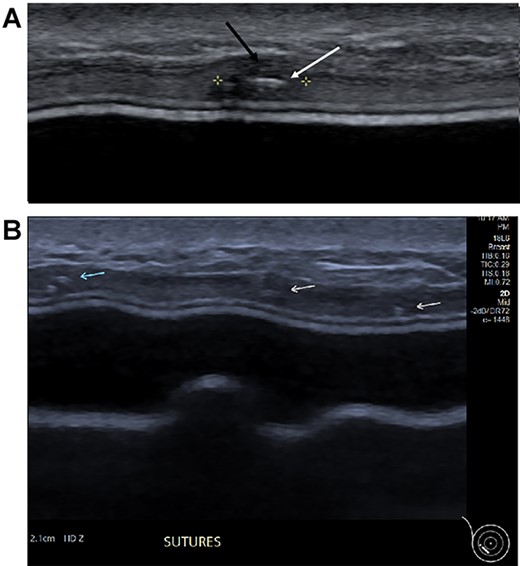

Clinical findings during follow-up were unremarkable until 2020, when she represented with a new lump in the reconstructed left breast neighbouring the mastectomy scar inferiorly. A 1 cm subcutaneous lump with no skin tethering, was palpable along the uniting suture line of the ADM-pectoral muscle. Imaging with ultrasound was indeterminate. This implant proximity rendered it unsuitable for core biopsy due to the high risk of iatrogenic implant perforation (Fig. 2). Subsequent MRI (Fig. 3) illustrated an 11 mm low signal lesion correlating clinically to the palpable lump with mild enhancement but indeterminate appearance.

Ultrasound of the left central breast identified an irregular mass on the capsule of the implant with a focus of hyperechoic calcification (arrow).